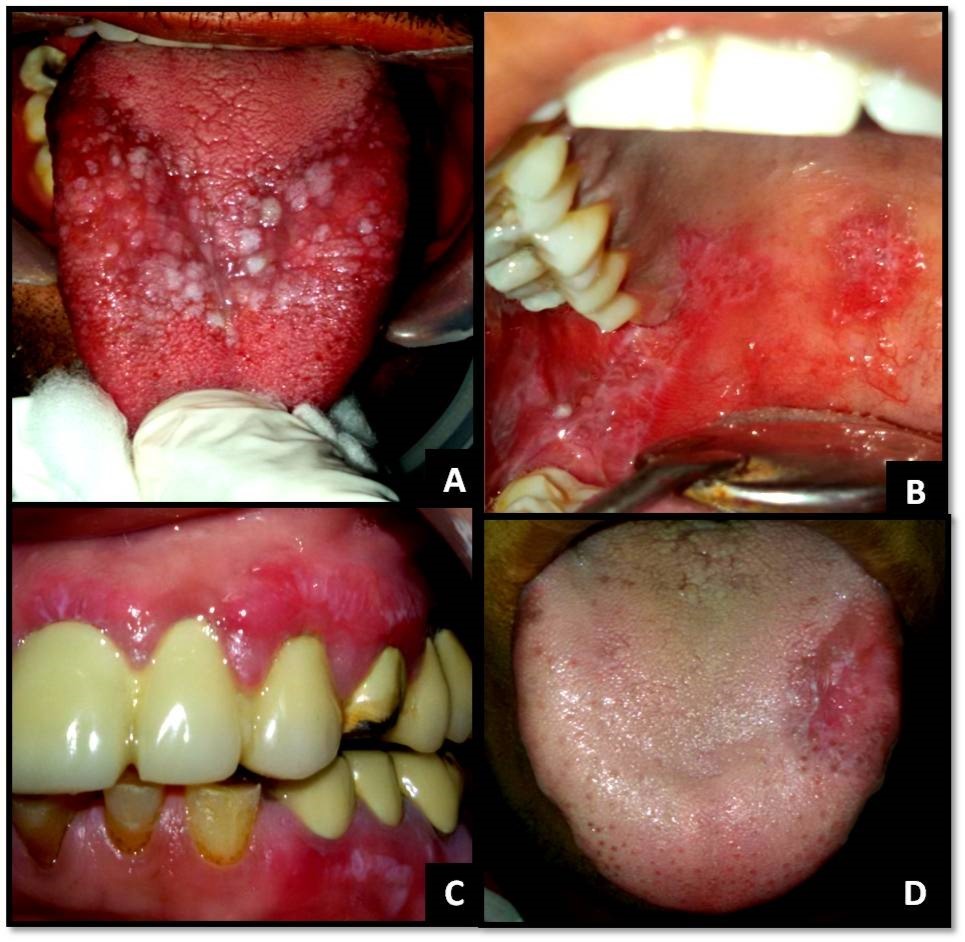

The clinical diagnostic criteria for oral lesions used in this study was- 1. The presence of keratotic, pinhead-sized, white, slightly elevated papules (papular lichen planus), which may be discrete or arranged in reticular (reticular lichen planus) or plaque-like (plaque-like lichen planus) configurations. 2. Atrophic lichen planus, characterized by thinning of the epithelium leading to the appearance of atrophic red areas within the white lesions. 3. Erosive (ulcerative) lichen planus, characterized by areas of well-defined ulceration within the above mentioned lesions. 4. Bullous lichen planus, characterized by the presence or development of bullous areas within the above mentioned lesions.1,2Representative images of OLP are shown in Figure 1 and Figure 2.

Figure 2.(A) Papular and plaque-like OLP on dorsal aspect of tongue; (B) Reticular and erosive OLP on the palate; (C) Reticular OLP on gingiva with desquamative gingivitis; (D) Reticular and erosive OLP on the tongue